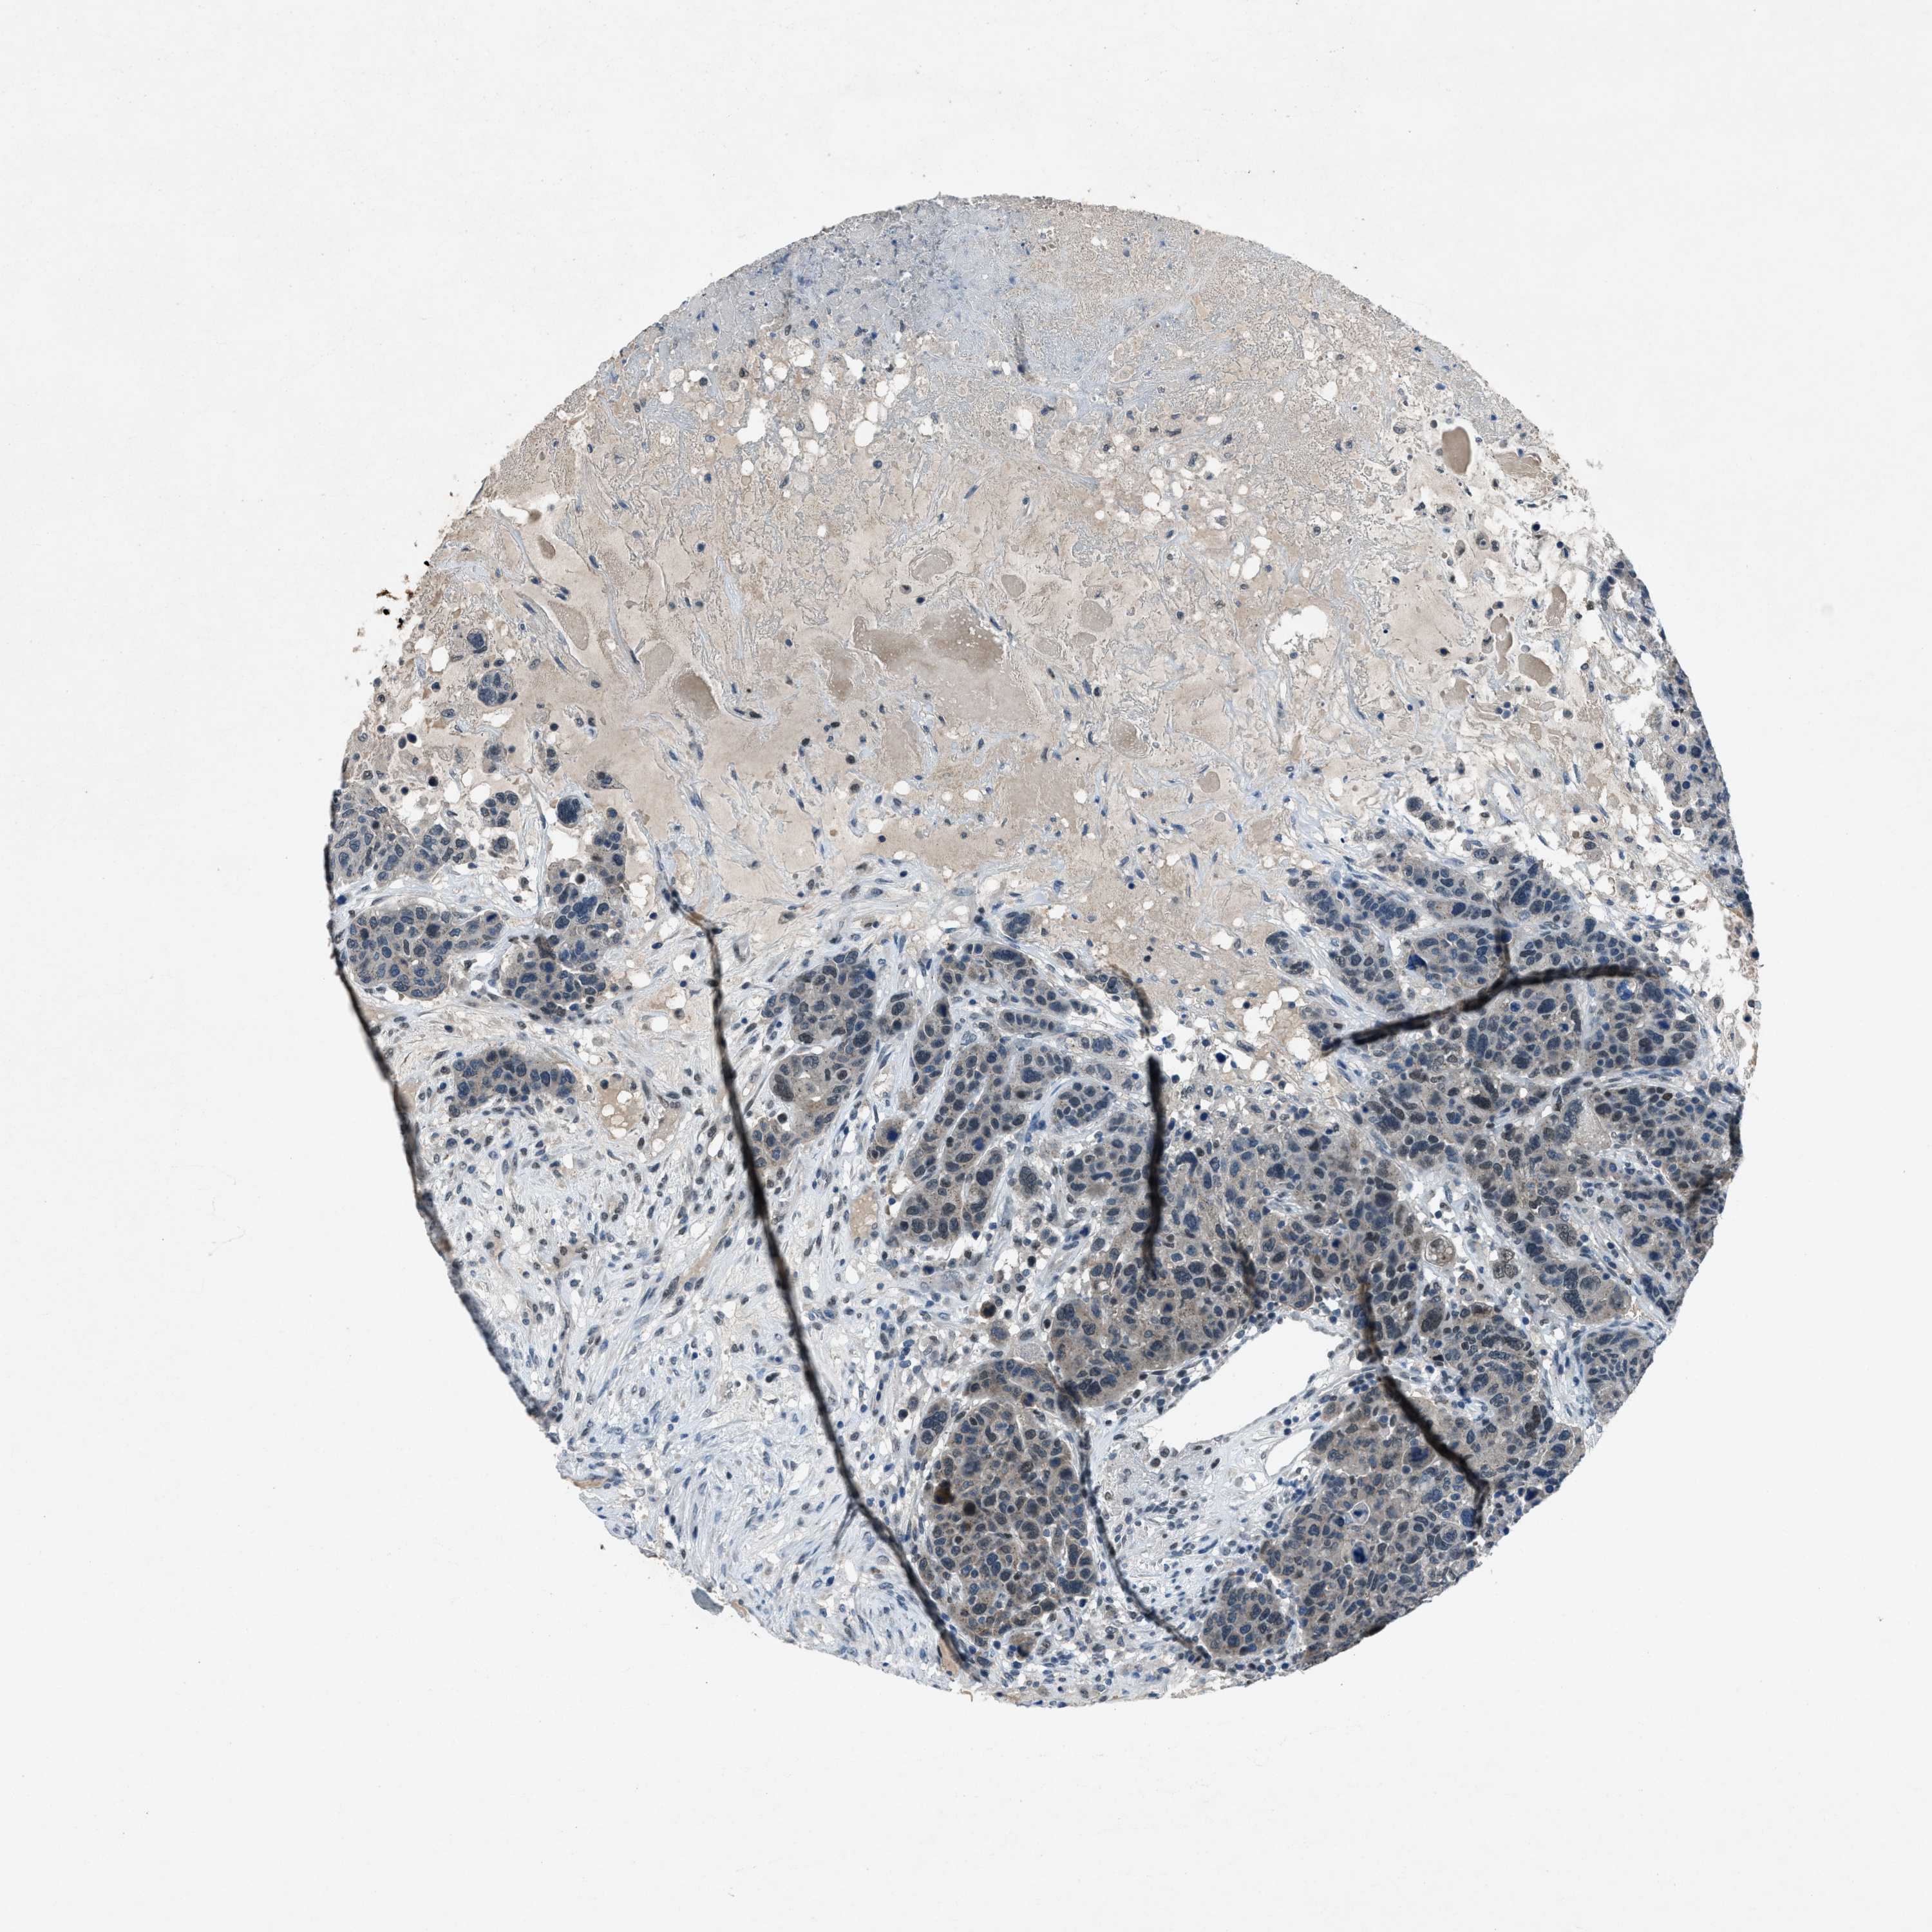

CANCER BREAST CANCER Show tissue menu

BRCA TCGA BRCA VALIDATION PROTEIN EXPRESSION

Breast cancer

Human cancer